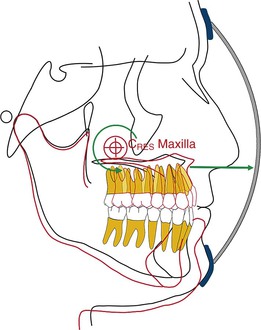

By changing the point of force attachment on the facemask or outer bow of the headgear, the vertical dimension of the face can be very nicely controlled. This is especially important in Class III patients with a long vertical dimension and a steep mandibular plane. Similarly, in Class III patients with a flat mandibular plane and a deep bite, a force below the level of the occlusal plane may be more desirable to rotate the mandible downward and backward (see Fig. 16-10). A line of force closer to the center of resistance of the midface will deliver a translatory force (Fig. 16-11) and a line of force closer to the occlusal plane has a rotational force (Fig. 16-12).

Figure 16-12 Force diagram showing the nature of the maxillary and mandibular change when the point of force application is at the level of the root apices of the maxillary teeth. CRES, Center of resistance.